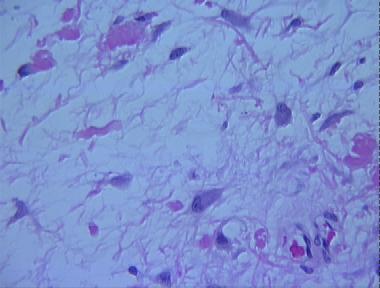

myxoid malignant fibrous histiocytoma

Histologic Features